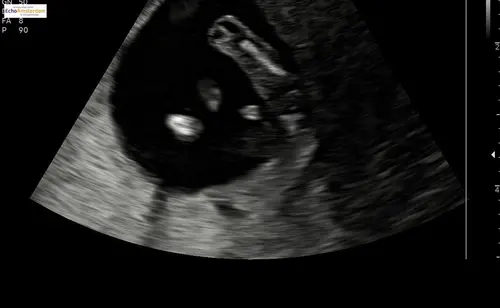

Wat denken jullie? Dit is 12 weken en 4 dagen 💖🩵

Jongen